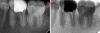

Kolchanov Опубликовано 21 февраля, 2013 Поделиться Опубликовано 21 февраля, 2013 Девушка 18 лет. Жалобы на боли от сладкого. Проходящие после устранения раздражителя. Уверенно тычет в 36. 36 представляет собой мезиальную и части щечной и язычной стенок характерного розово-бурого окраса, остальное - пломба из чего-то композитного, скорее хим отверждения. Перкуссия безболезненна, холодовая как-то неопределенно, то ли есть, то ли нет.Делаем снимок когда лечила не помнит, но в компе нашел еще один снимок с августа прошлого года. Завтра еще придет в 18.00.Прошу помочь советом.Лезть или оставить аккуратно заменив пломбу? 1 Ссылка на комментарий

anvladd Опубликовано 21 февраля, 2013 Поделиться Опубликовано 21 февраля, 2013 А мне показалось что кариес и в 5 дистально и в 7 медиально.и еще походу в7. фиссурки глубокие и уже наверняка кариес там. Фото есть? Ссылка на комментарий

Kolchanov Опубликовано 10 апреля, 2013 Автор Поделиться Опубликовано 10 апреля, 2013 Вот такая вот фигня с этим зубом получилась. Надо оно было ему, нет, теперь уже все равно.С гидороокисью в дистальном она походила с месяцок+ сегодня удалось таки залезть в мезиально-язычный. Мезиально-щечный долбил пока видел, а потом плюнул. Там и так фуркация слезами плачет, судя по снимку.Передал отправил к ортопедам. Чую штамп будет там... Ссылка на комментарий